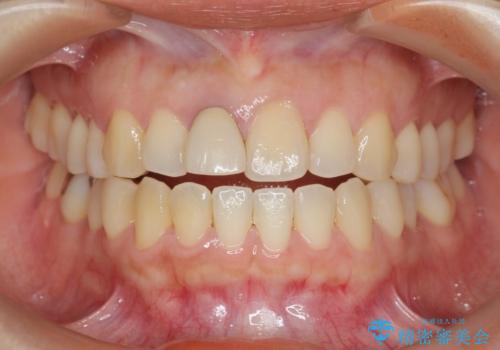

オーダーメイドで造る、自然な前歯セラミッククラウン

- 幼少期に前歯をぶつけて歯が折れ、神経の治療・クラウン治療を行った。グラつきと見た目の改善を希望して来院されました。

精密な仮歯をいれ、歯周組織を整えるとともにファイバーコア築盛、シェードテイキングを行い見た目に自然なジルコニアクラウンを製作していきます。

ジルコニアクラウンの中でも当法人のグレードの高い、スペシャル・エクセレントプランはオーダーメイドで色調を合わせることで周囲の歯に馴染んだ自然な歯を製作することのできるプランです。